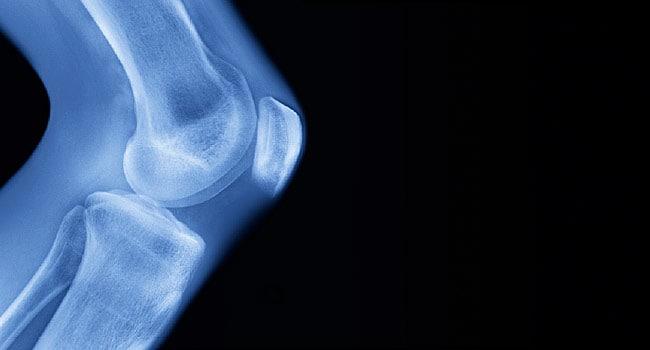

အဆစ်ရောင်နာ (Arthritis) ဆိုတာ အဆစ်တွေကို ထိခိုက်စေနိုင်တဲ့ ကျန်းမာရေးပြဿနာ တစ်မျိုးပါ။ အဆစ်တွေ နာကျင်တာ၊ ရောင်ရမ်းတာတွေ ဖြစ်စေနိုင်ပါတယ်။ လှုပ်ရှားဖို့ ခက်တာ၊ တက်တက်ကြွကြွနေဖို့ ခက်တာမျိုးတွေကိုလည်း ခံစားရနိုင်ပါတယ်။ အဆစ်ရောင်နာတွေက အမျိုးမျိုးပါပဲ။ တစ်မျိုးစီတိုင်းမှာ မတူညီတဲ့ လက္ခဏာတွေ ခံစားရနိုင်ပါတယ်။ အဆစ်ရောင်နာ အမျိုးအစားကို လိုက်ပြီး ကုထုံးတွေလည်း ကွာခြားနိုင်ပါတယ်။ အဆစ်ရောင်နာ က များသောအားဖြင့် အသက်အရွယ် ကြီးရင့်သူတွေမှာ အဖြစ်များပါတယ်။ အမျိုးသားတွေမှာ ဖြစ်နိုင်သလို အမျိုးသမီးတွေ၊ ကလေးတွေမှာလည်း ဖြစ်နိုင်ပါတယ်။ အရွယ်သုံးပါးစလုံး ခံစားရနိုင်တဲ့ ကျန်းမာရေး ပြဿနာပါ။ အဆစ်ရောင်နာ (Arthritis) ဆိုတာ အဆစ်ရောင်နာ ဆိုတာ အဆစ်တွေ ( အရိုး တစ်ခုခုနဲ့ တစ်ခု ဆုံပြီး လှုပ်ရှားမှုတွေ လုပ်ဆောင်နိုင်တဲ့ နေရာ) မှာ ထိခိုက်စေတဲ့ ကျန်းမာရေး […]